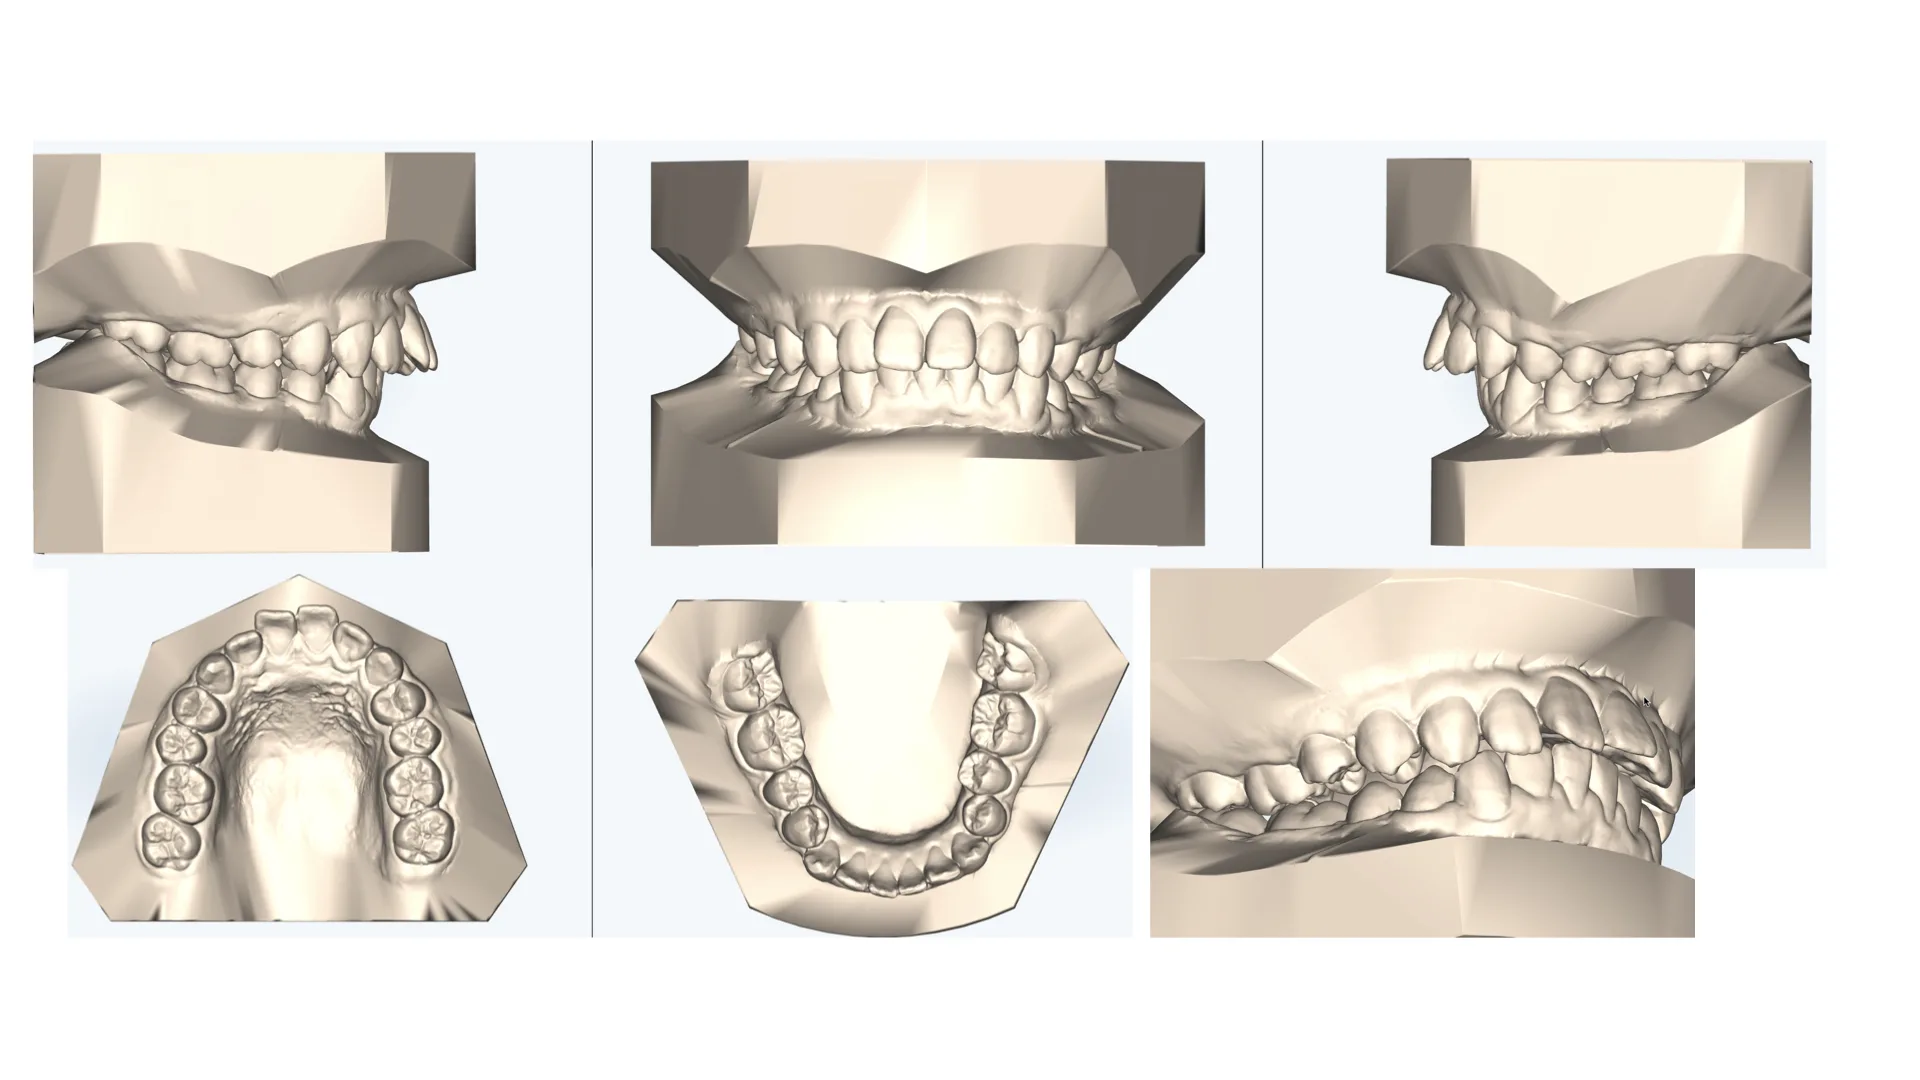

症例 上顎前突 抜歯